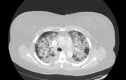

Many cases related to vaping-associated lung injury have recently been reported to the Center for Disease Control (CDC). It is, therefore, important for clinicians to be aware of this disease. Here, we present the case of a 46-year-old female patient, who had recently started vaping. She presented to the hospital with dyspnea; since her condition deteriorated quickly, she was mechanically ventilated for acute respiratory failure. When a computed tomography angiography (CTA) chest was performed, patchy alveolar opacities were seen throughout both lungs. The patient's workup for infectious and cardiac etiology was negative. She was diagnosed with vaping-associated lung injury. Later, she recovered and was discharged to a rehabilitation center.

Figure 1. CTA chest showing bilateral alveolar opacities.

CTA: Computed tomography angiography